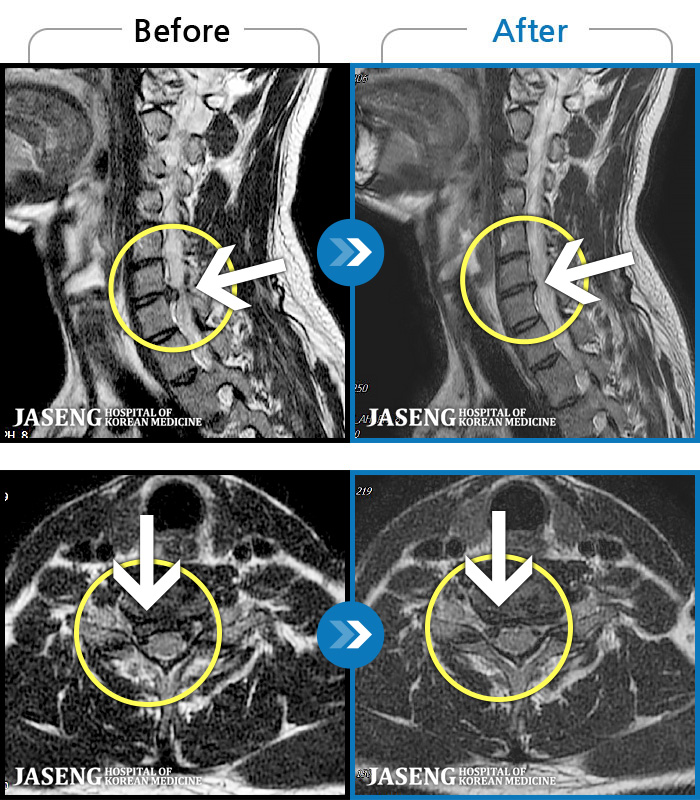

MRI ġ

1,237 MRI ũ ʸ Ȯϼ.